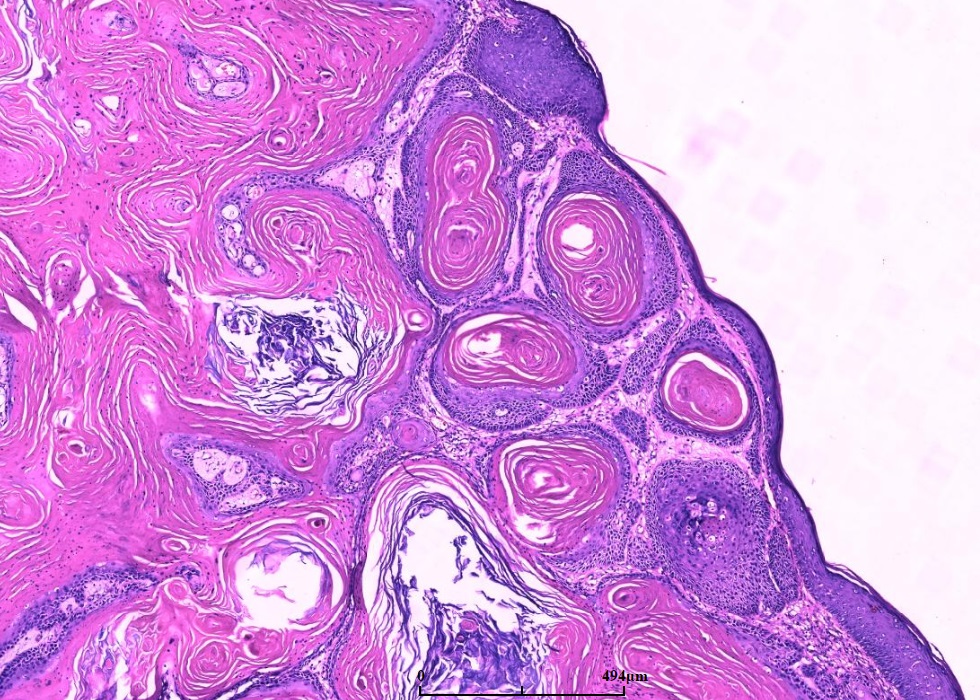

随着病变进展,中央出现火山样结构,内含角化细胞及角化物,无颗粒细胞;

鳞状上皮巢不规则向深部浸润,但轮廓光滑,一般不会超过附属器的水平,深部的上皮细胞巢或上皮脚顶端可出现角化珠和上皮内中性粒细胞微脓肿;

邻近的表皮常呈外生性突起,形成一个唇样轮廓;